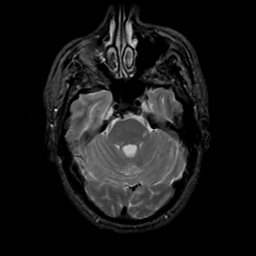

MR Study #20 October 6, 1991 -- Slice #14

[Home][Help][Clinical][Tour 1][Tour 2] Slice 14